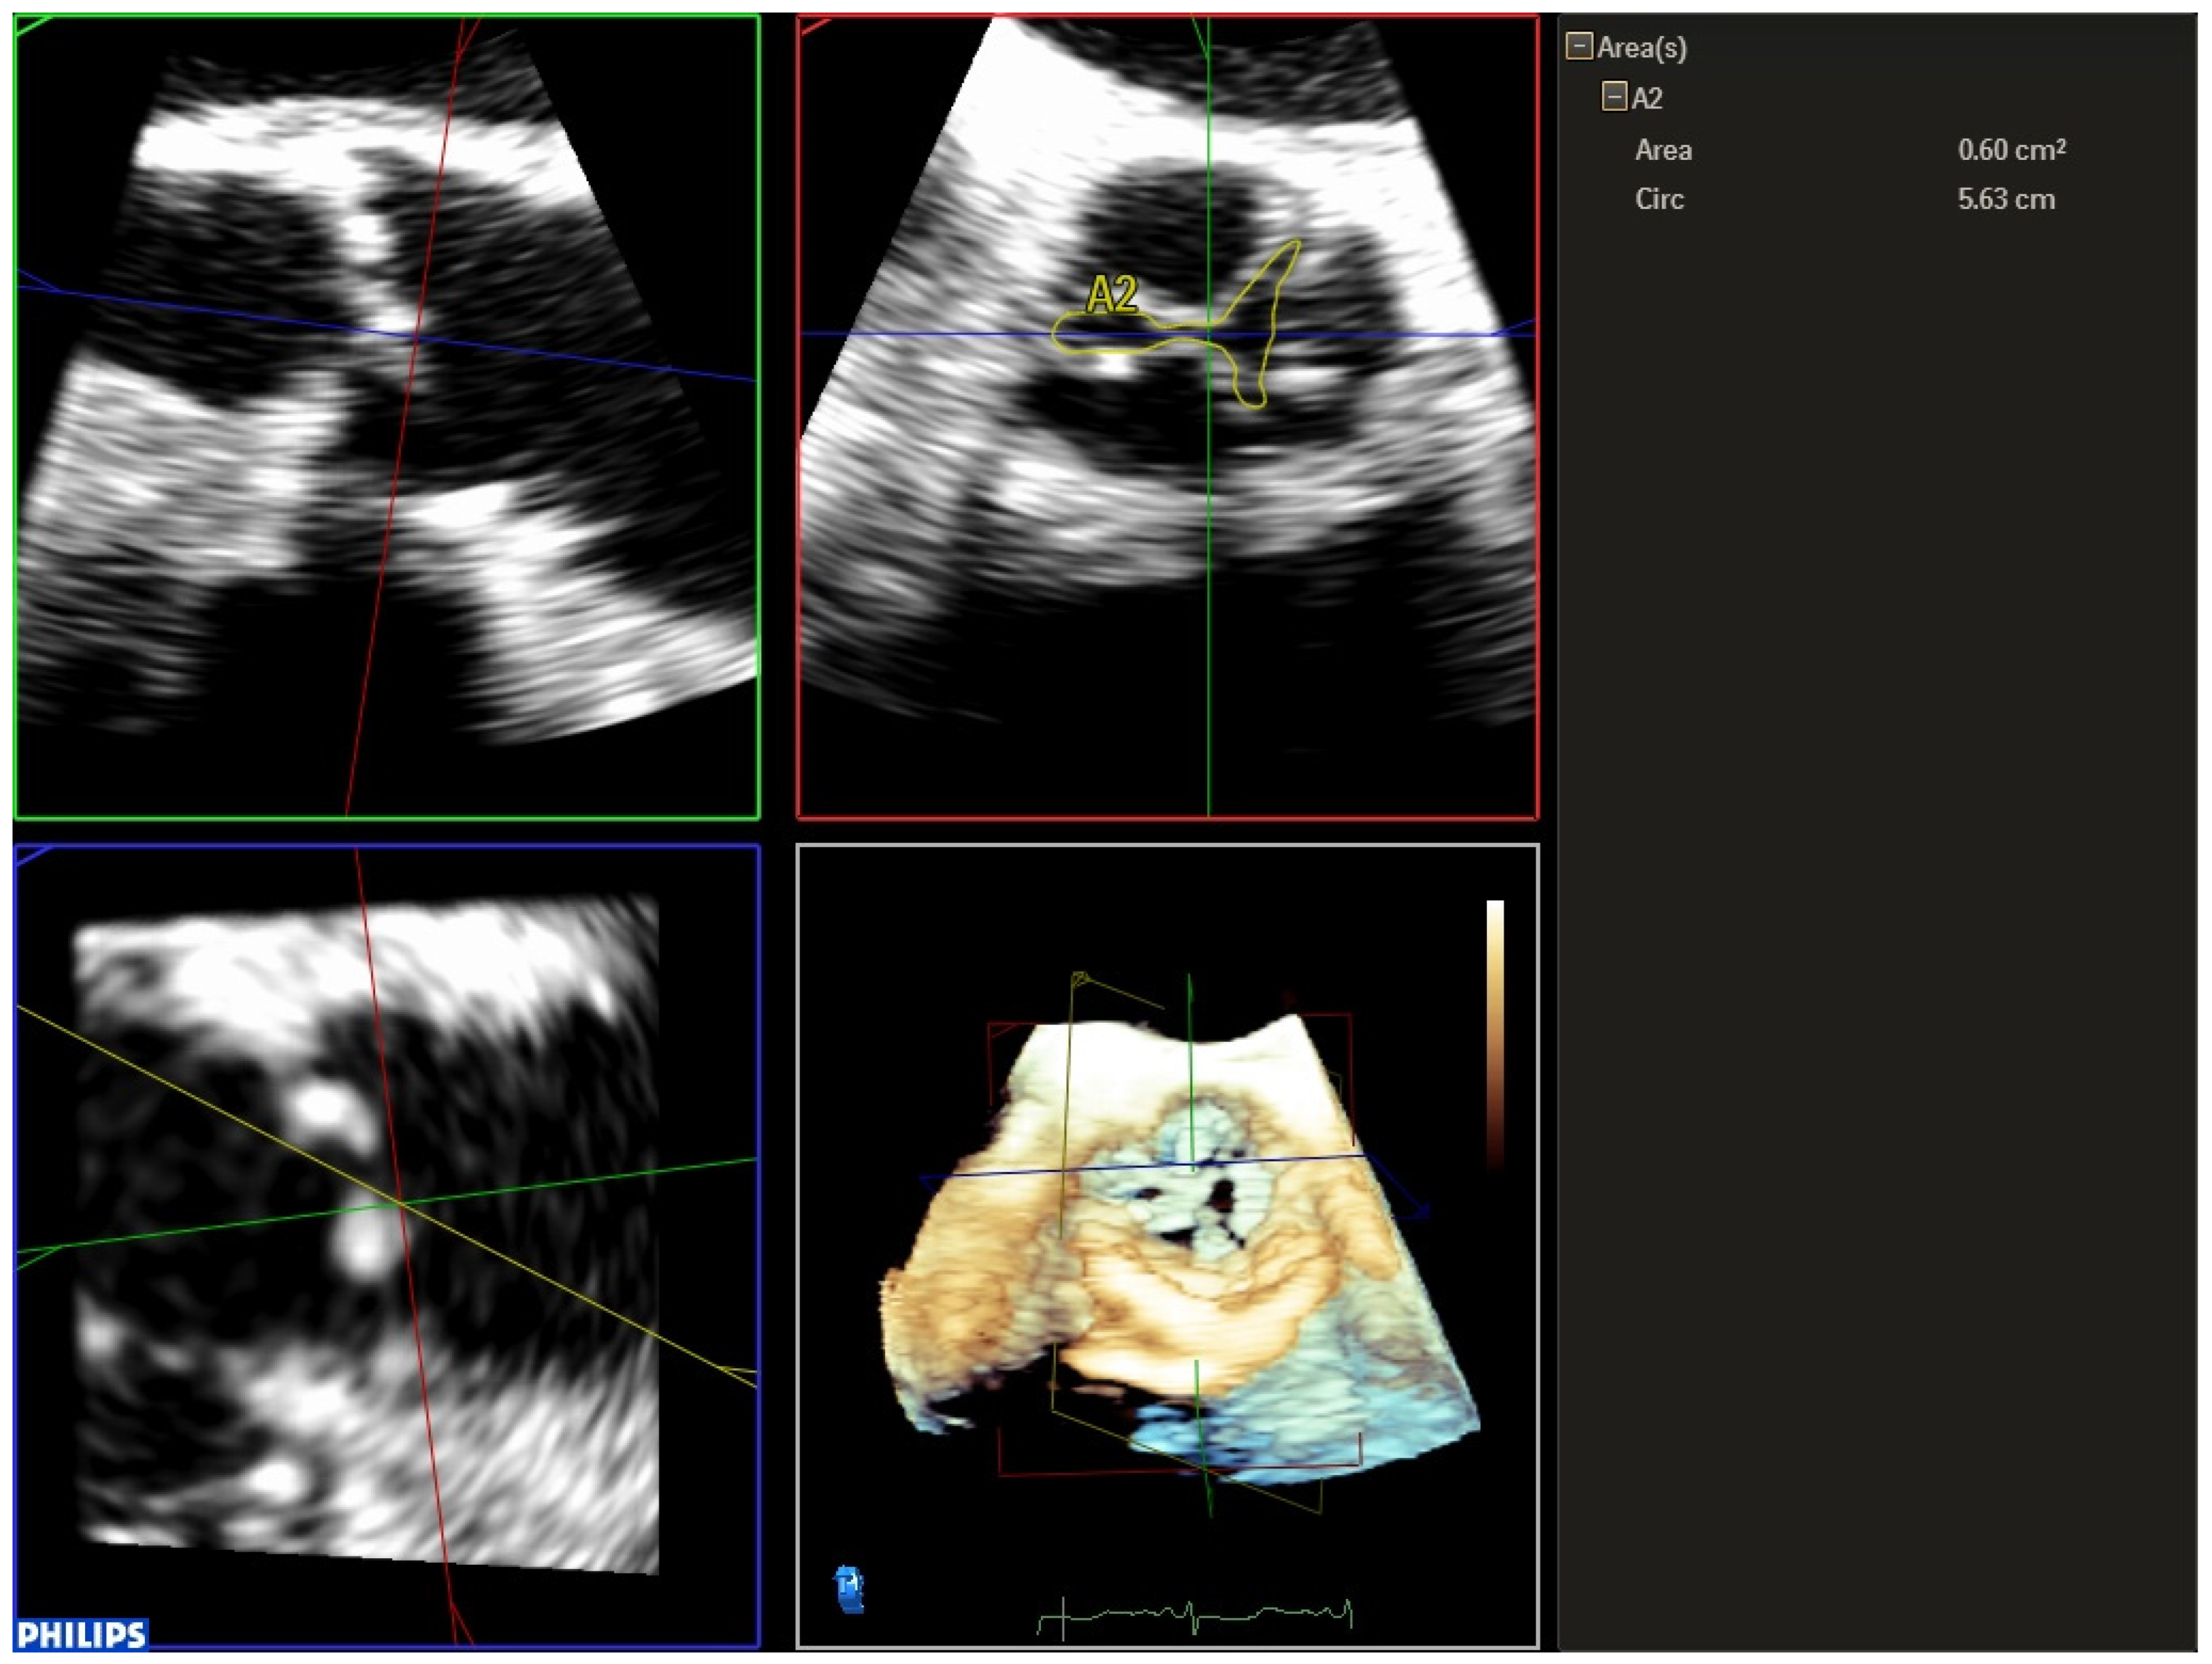

| 1 | Three-dimensional TEE allows us to accurately evaluate the aortic valve morphology and measure the valve annulus prior to TAVR implantation, helping us to choose the appropriate size of the prosthesis, especially useful in cases where the cardio-CT is not of adequate quality. |

| 3 | Three-dimensional TEE is the best technique to detect and quantify perivalvular regurgitation after TAVR implantation, a fundamental aspect in deciding whether immediate valve postdilation is needed or not. |